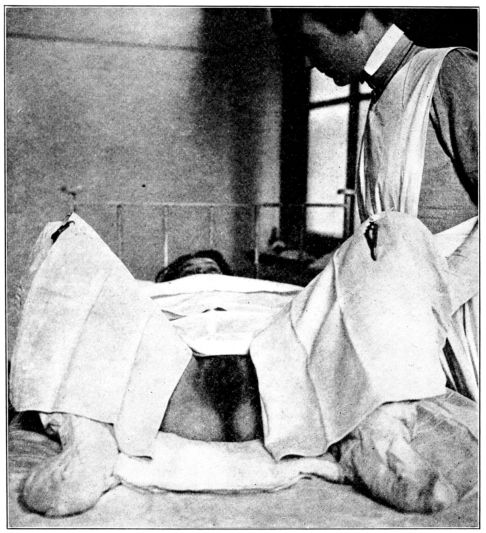

| 74. | Preparing patient for vaginal examination or delivery | 250 |

| 75. | Patient draped for vaginal examination | 251 |